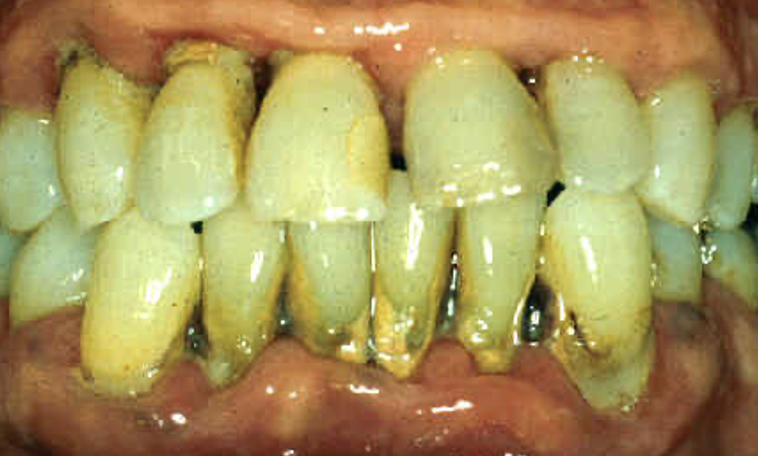

<p>outline notable aspects about this patient</p>

outline notable aspects about this patient

• chronic periodontitis

• loss of contour of gingival tissues

• lots of calculus

• likely mobility issues

• likely periapical infections

• likely halitosis